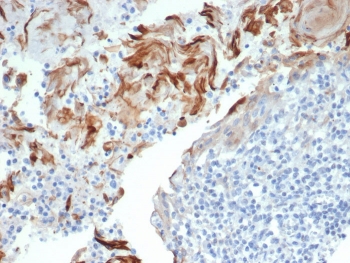

IHC staining of TrkC / NTRK3 antibody (clone NTRK3/7140). FFPE human breast cancer tissue shows HRP-DAB brown membranous and cytoplasmic staining in tumor epithelial cells, consistent with receptor tyrosine kinase localization. Staining of formalin-fixed tissues requires boiling tissue sections in pH 9 10mM Tris with 1mM EDTA for 20 min followed by cooling at RT before testing.